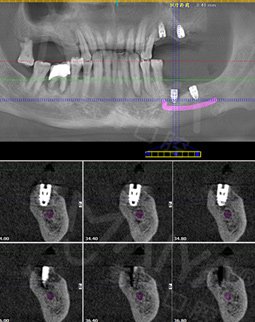

2018年4月 完成种牙,感谢麦芽口腔

经过近一年的体验,他们每个细节都做的非常好,你牙能不能种,种在什么地方,什么时间种,什么时间结束,每次种牙都根据你的身体状况来决定,而且包括复诊、戴牙冠,每个环节都做的很到位。

因为我还有高血糖,他们测定血糖高低,身体情况允许的情况下再决定种牙。这个细节让我感到很感动,我就宁可时间也长一点,但一定要把牙种好,医生和护士都把病人当亲人看待,非常好,种牙之后我吃东西也舒服很多,再也不用为假牙而苦恼了,而且和真牙真的没有什么区别,我相信科学,相信郑教授的团队。

2017年10月 完成种牙,感谢麦芽口腔

一想到中国人的春节,就是一家人热闹的吃个团圆饭,没有一口好牙齿怎么行,所以就迫切的希望早点种上牙齿。郑院长为我定制了“MAC数字化精确微创舒适种植”技术,但是我本身血糖高,考虑到我身体因素,分批次种植,经过了一系列检查后,就开始去手术室种牙,真的一点也不疼,舒适的种牙体验,就像被蚊子“叮”了一下牙就种好了,对于我来说,种牙过程很轻松,全程无痛,种完后也不肿不痛的,术后定期复诊就好了,我当天回去没有什么不适感,而且吃东西也不影响。